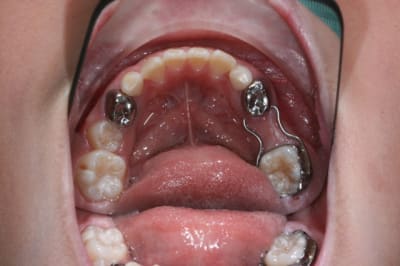

antoine 4 ans1/2

vu en Mars 2007 :traitement 55 -85-51-61

et commencé

- couronnes pedo(54-64-65-75) sur dts vivantes: trop délabrées pr pouvoir reconstituer correctement en retrouvant une DV correcte mais de la dentine réactionnelle,pas d'infection

-compos sur 53 et 63

-les anterieures je ne sais pas encore...